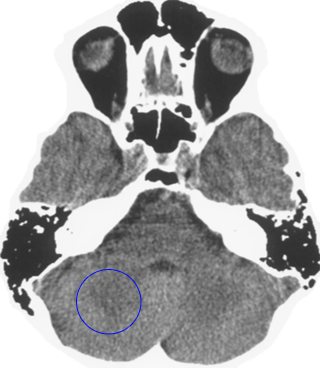

Which is the brain relais that is shown here? 25 Questions each cycle, try more!

Question 1 of 25